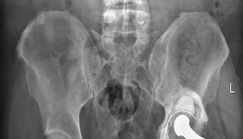

Case Title: The Use of Acetabular Augments for Revision Total Hip Arthroplasty Demographics Age: 71 years old…

Demographics Age: 71 years Sex: Male BMI: 26.2 Relevant Past Medical History Principal pathologies: Non-insul…